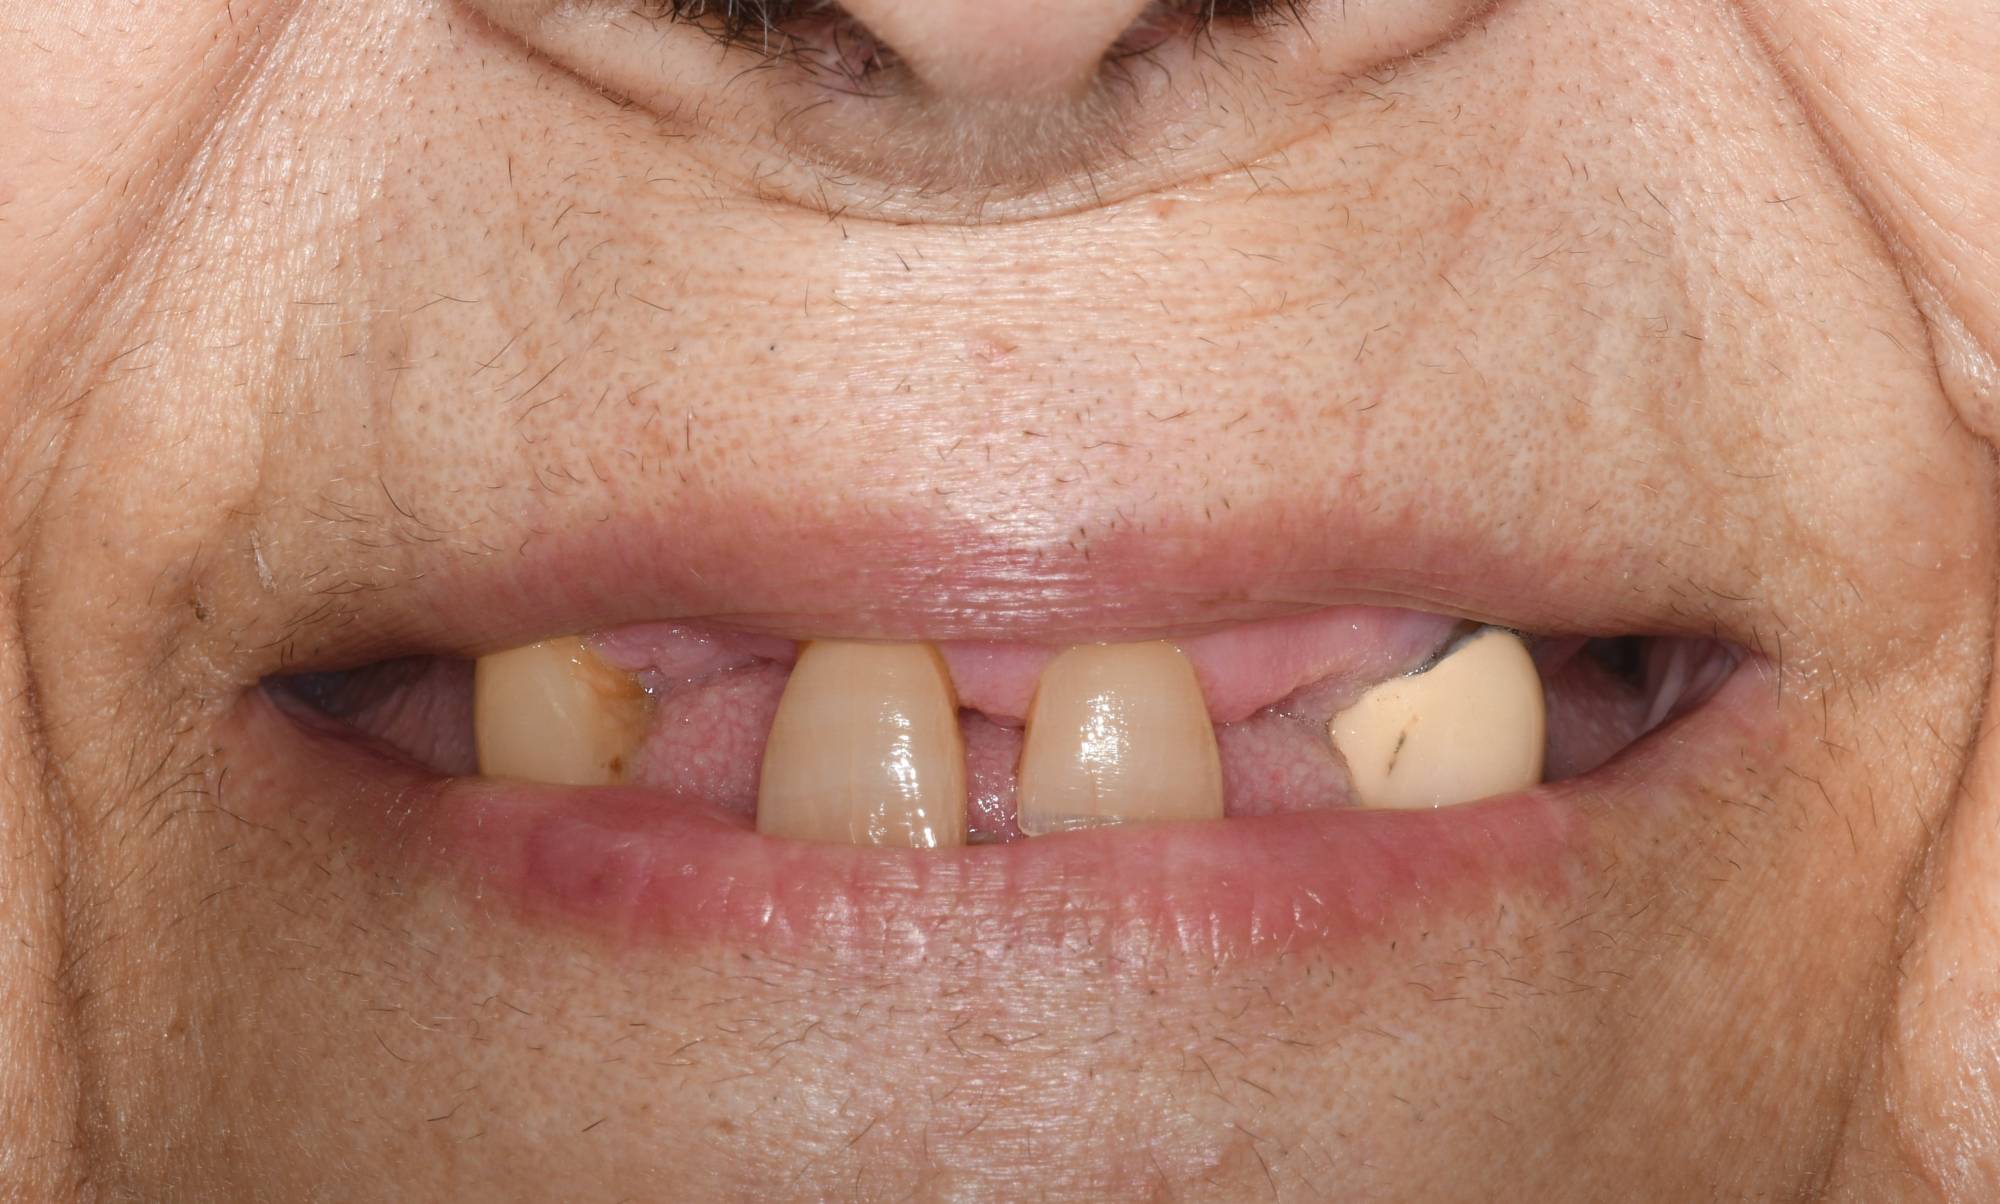

L'impianto dentale osteointegrato è una sorta di radice artificiale che si inserisce nell’osso del paziente, per rimpiazzare un dente mancante.

L'impianto, oltre a essere un metodo sicuro, garantisce l'aspetto esteriore e la piena funzionalità di un dente naturale. Oltre a ciò, mantiene l’integrità dell’osso, non va ad intaccare i denti adiacenti - come invece farebbe un ponte - e migliora l’estetica facciale prevenendo la perdita ossea.

Gli impianti sono molto versatili e possono essere usati per sostituire un dente singolo, più denti fissi o addirittura un'intera arcata. Inoltre, possono essere inseriti sotto una protesi mobile per stabilizzarla migliorandone il comfort.